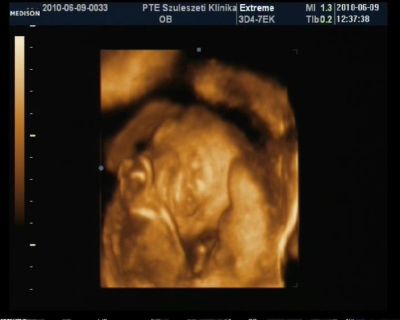

100%-ra ki lehet jelenteni hogy kislány

Mérete 23héttel egyezik ezért viszahivott 2 hét mulva csak egy mérésre hogy biztosak legyünk a terhességi korban. Szoktak ilyen 4D-n csinálni??

Szerintetek nem pofátlan dolog ha viszek neki desszertet meg egy kávét majd?Kaptam képet, dvd-dt és szakvéleményt. BDP 55mm (remélem jol emléxem mert a kociban van a papir reggle ugyis kell a mappám mert cukorvérvételre megyek ) A grammba biztos vagyok 536gramm

Aranyos husis, nagyo sokat szopizza az ujjacskáját! Készitettem képet nem épp a legjobb minőség, nem tudom mi van a géppel. De azért felteszem ide

Csak kiveszitek. De én ugy vélem tiszta apja